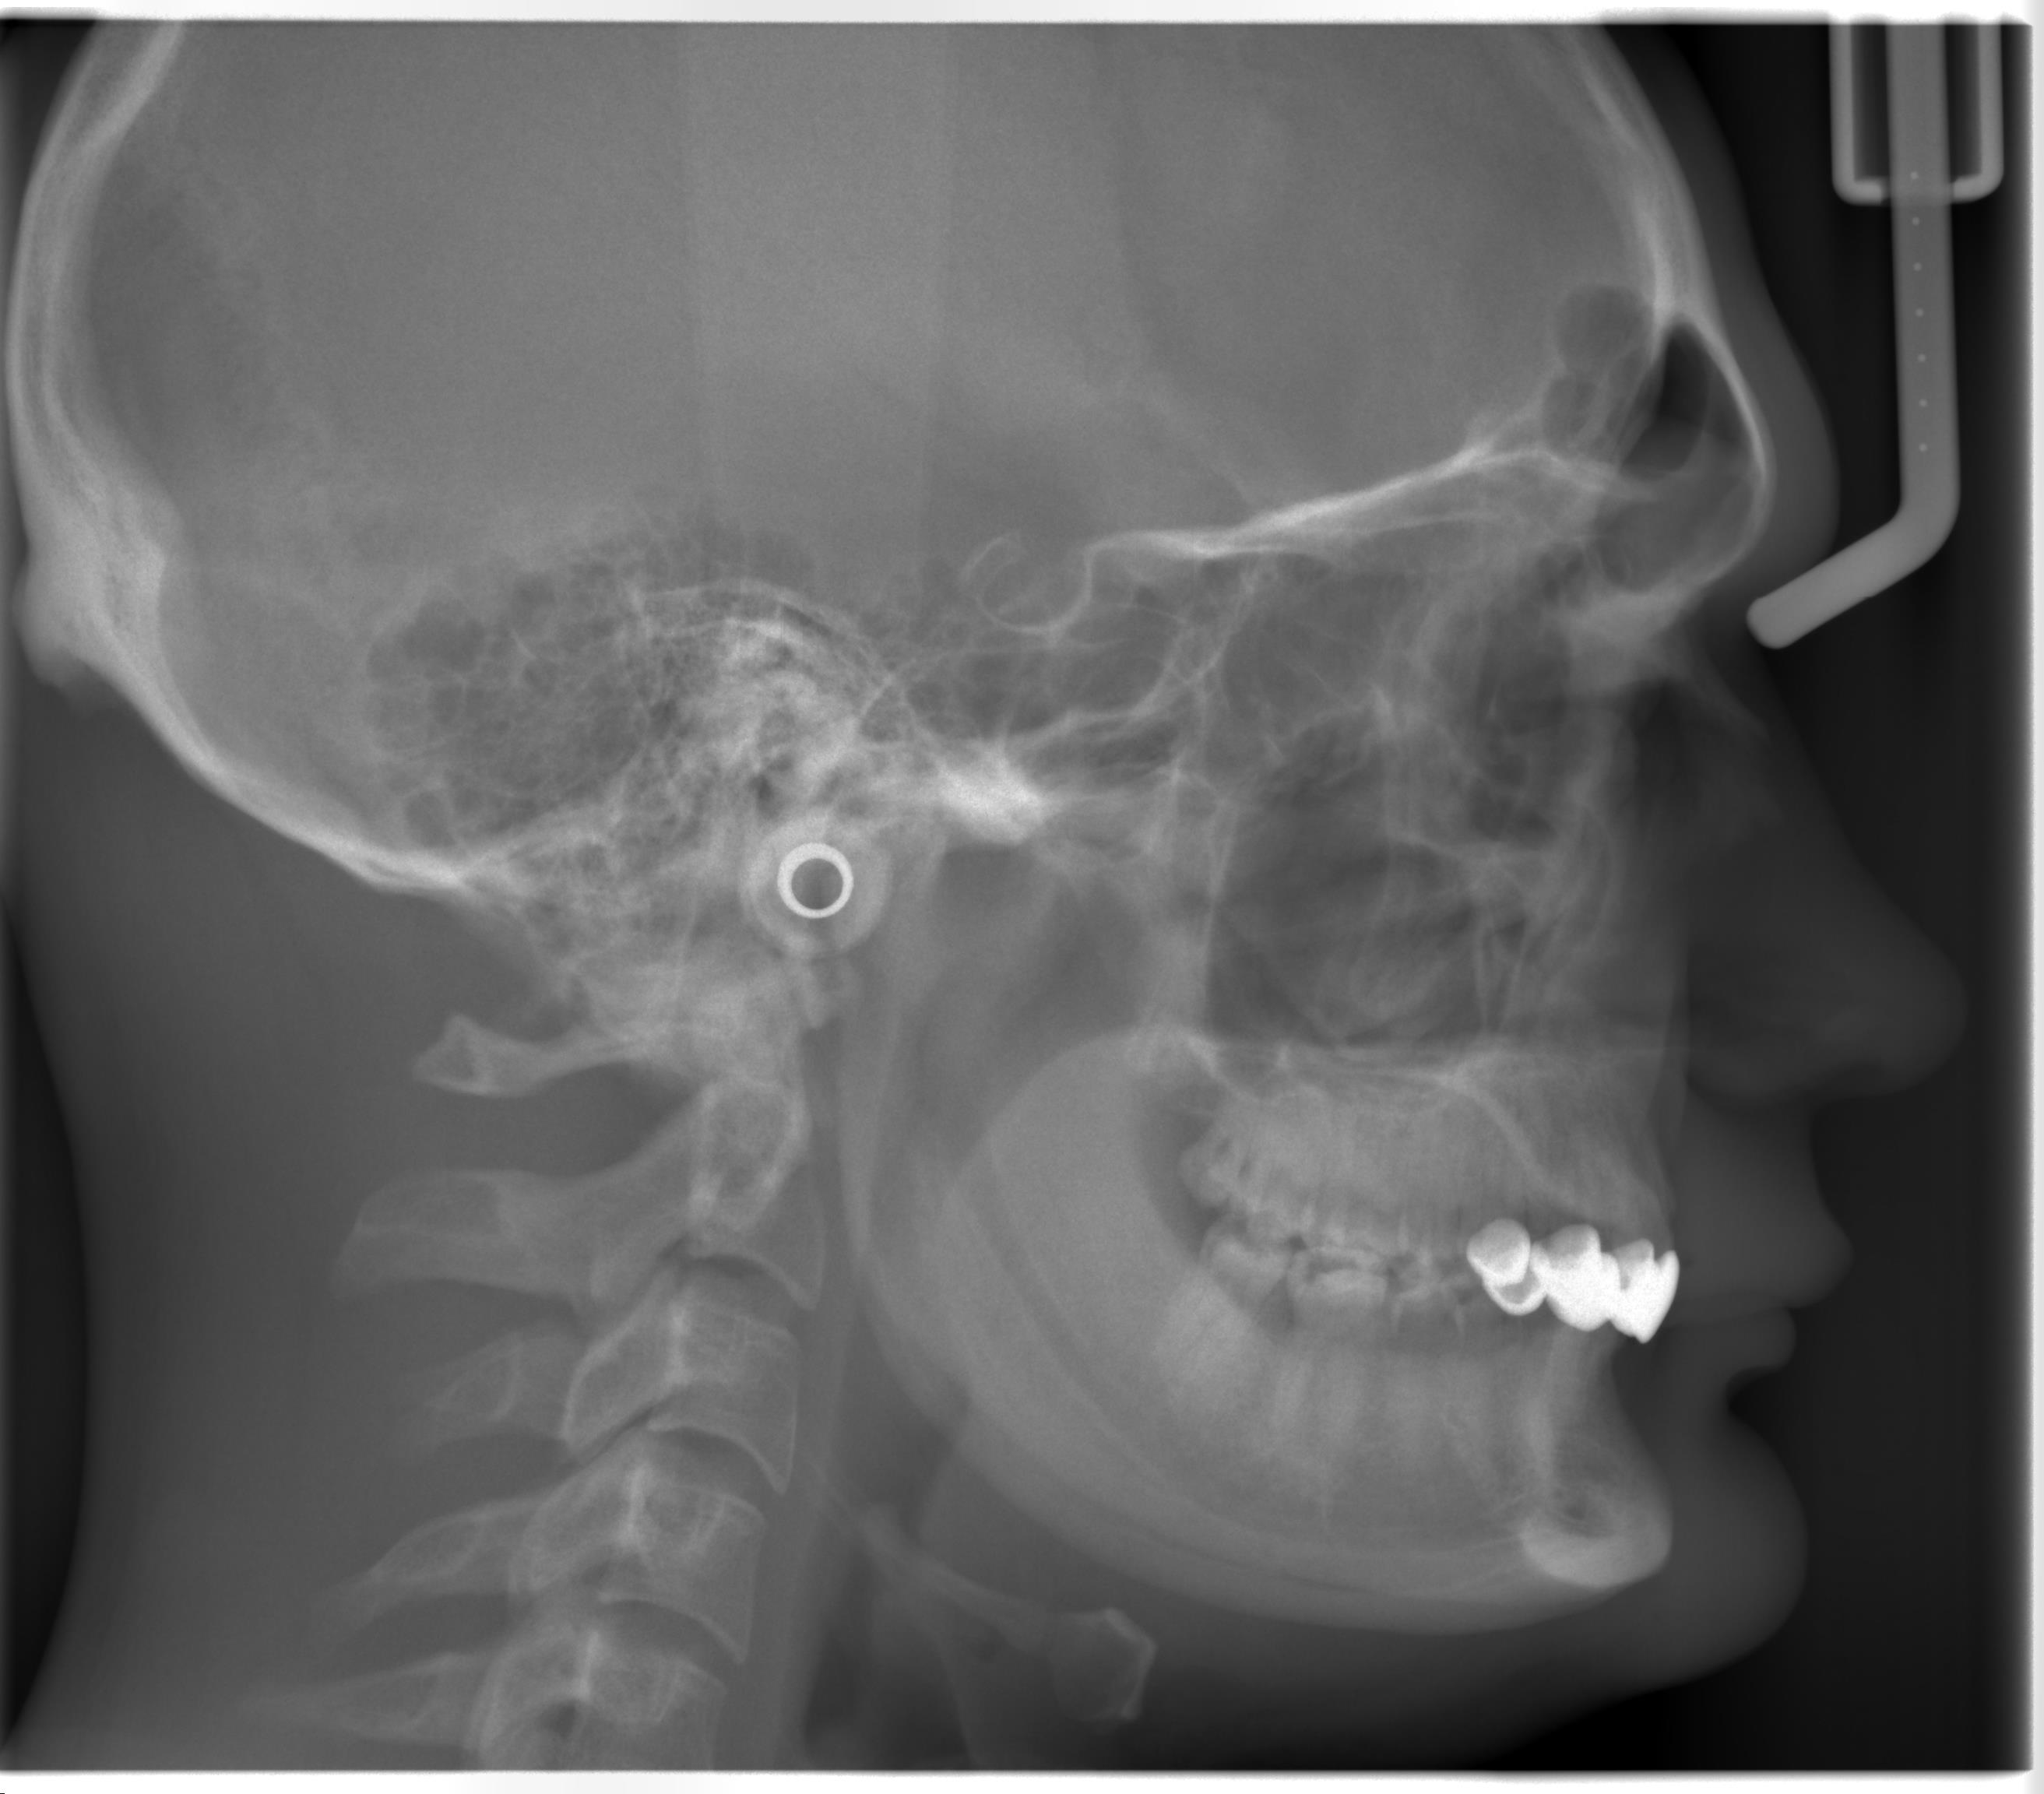

Looking for technical input from people who've researched this or been through it. CONTEXT - Male, adult, Class II retrognathic - 1 month into pre-surgical ortho - Bimax (Le Fort I + BSSO) in ~11 months - Surgeon: experienced Italian maxfax, CAD/CAM + custom PEEK workflow THE ISSUE My lateral mandibular profile has what I'd call a "banana shape" — no defined transition between ramus and body. Instead of a clear L-shape with a sharp gonial angle, the whole lower jaw reads as one continuous curve from ear to chin. Key features: - Obtuse gonial angle (visually >130°) - Undefined gonion, no "hook" - Poor cervicomental angle - Recessed pogonion - Short/thin mandibular body - Convex lower third overall Pre-op ceph attached. QUESTIONS 1. Etiology: mandibular hypoplasia, hyperdivergent pattern, backward rotation secondary to maxillary deficiency, genetic micrognathia, or combination? 2. Looking at the ceph: how much of the "banana" is realistically fixable by bimax alone (advancement + CCW rotation), and how much still requires alloplastic augmentation? 3. For those who went single-stage (bimax + custom PEEK jawline in one surgery): how was the VSP workflow? Was the implant designed on the post-BSSO virtual model? How was the fit? 4. Any case studies or threads with similar pre-op bony morphology would be hugely appreciated. Already decided on single-stage with my surgeon, so not looking for "do bimax first and see" answers. Trying to understand the underlying anatomy better for the next consult. Ceph analyses welcome. Thanks.

Hey everyone, looking for technical input from people who've researched this or been through it themselves. STATS / CONTEXT - Male, adult - Skeletal Class II retrognathic - 1 month into pre-surgical orthodontics - Bimax (Le Fort I + BSSO) planned in ~11 months - Surgeon: well-known maxfax in Italy, experienced with CAD/CAM workflow and custom PEEK implants THE ISSUE My lateral mandibular profile has what I've been calling a "banana shape" — meaning there's no defined transition between ramus and body. Instead of the classic L-shape with a clear gonial angle, the whole lower jaw reads as one continuous curve from the ear down to the chin. Key features I can identify: - Obtuse gonial angle (visually >130°) - Undefined/rounded gonion, no "hook" - Weak jawline-to-neck transition (poor cervicomental angle) - Recessed chin (pogonion) - Short/thin mandibular body in lateral view - Overall convex lower-third profile Attaching my pre-op lateral cephalometric x-ray so you can see the bony architecture directly (soft tissue aside). QUESTIONS 1. What is the actual etiology of this morphology? Is it primarily: a) mandibular hypoplasia (small mandible overall) b) high mandibular plane angle / hyperdivergent pattern c) backward mandibular rotation secondary to maxillary deficiency d) genetic micrognathia e) combination? 2. Looking at the ceph: how much of the "banana" is realistically fixable by bimax alone (advancement + CCW rotation) vs. how much will still require alloplastic augmentation afterwards? 3. For those who went single-stage (bimax + custom PEEK jawline implant in the same surgery): how was the VSP workflow? Was the implant designed on the post-BSSO virtual model, and how did the fit turn out? 4. Any references, case studies, or before/after threads with similar starting bony morphology would be hugely appreciated — especially from people who had a similarly "curved" mandibular outline pre-op. Not looking for "just do bimax first and see" answers — I've already decided on single-stage with my surgeon and I'm trying to understand the underlying anatomy better so I can have a more informed discussion at the next consult. Cephalometric analyses / measurements welcome. Thanks in advance.View attachment 4953843

For the banana shape iam not sure lol it is a bit odd but I wonder if it’s only cuz it’s X-ray and not CT. We’d need to see CT to see full ramus to mandible transition

And trust me, IRL it's a fucking banana jaw too. Not

a 2D artifact — same curved outline from ear to chin

in real life, no defined gonion. Ceph just confirms

what the mirror shows.

Still agree CT would give a cleaner read on the

ramus-body transition though, good call.

ccw makes no sense. your OPA and mandibular plane angles are very flat.

You need to make your jaws longer and more forward. decompensation would be needed too, to increase the overjet

A complicated case. The surgeon will probably do a 2-piece lefort to rotate the forward part of the upper jaw upwards for the deep bite, then some downgraft and vertical genio